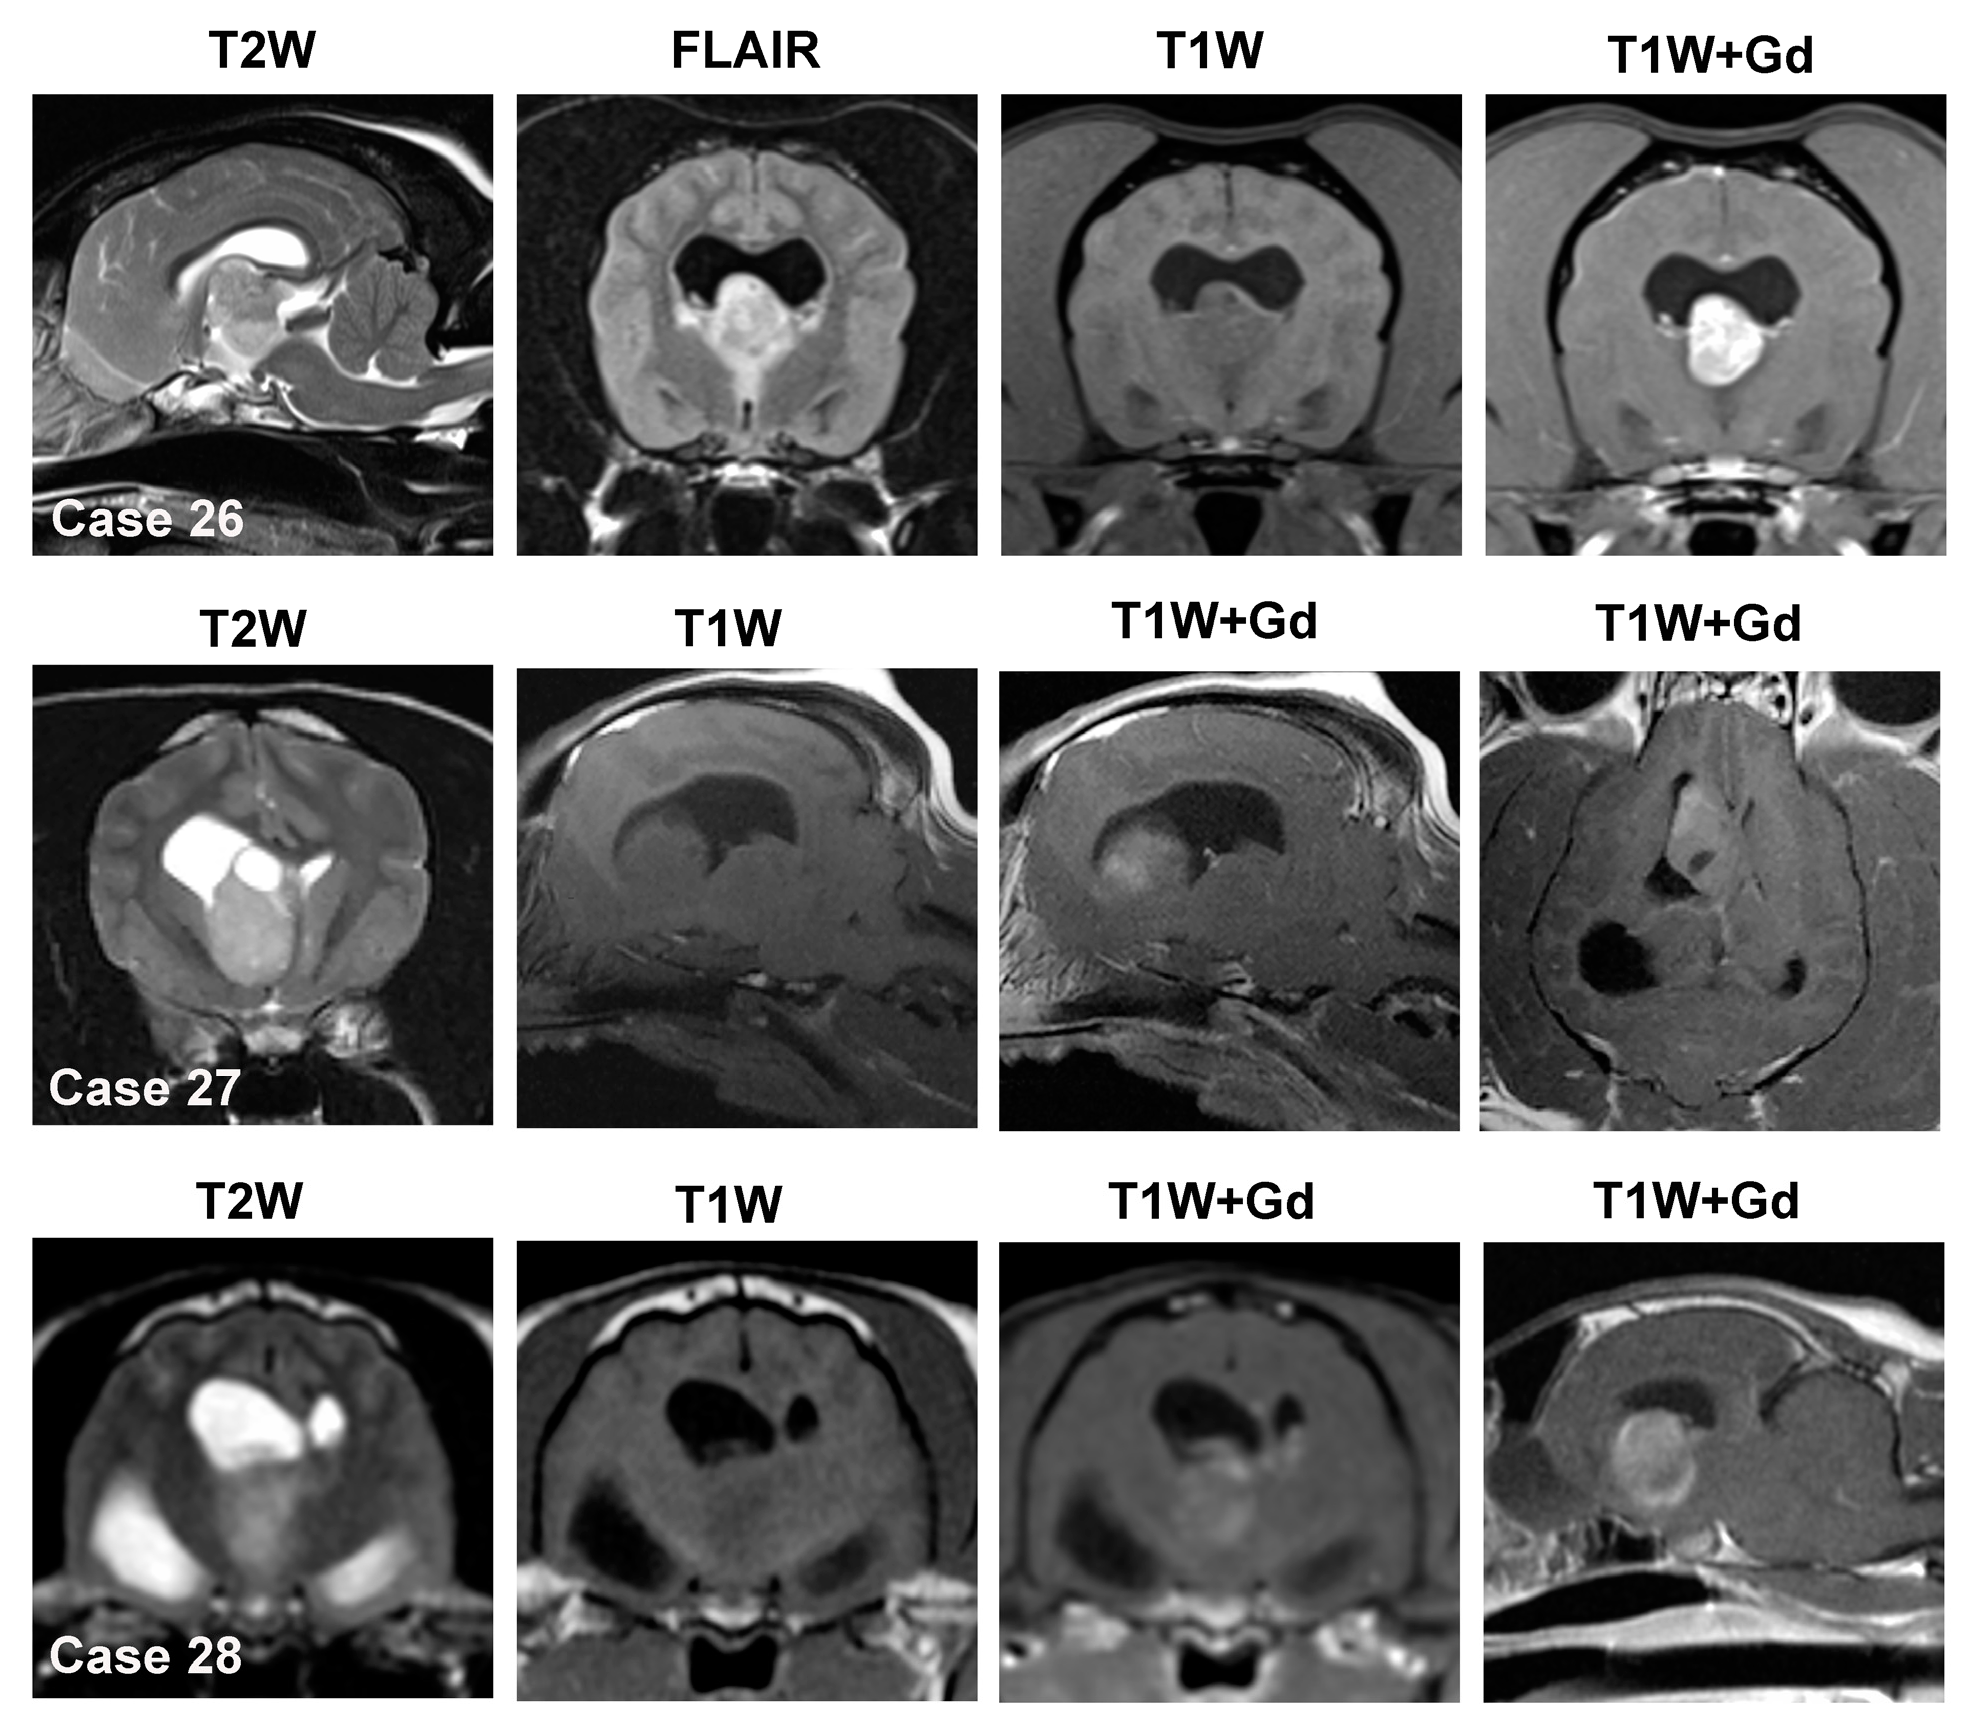

Figure 7.

MRI features of solitary intraventricular masses. Case 26—canine choroid plexus papilloma involving the 3rd ventricle and interventricular foramina. The tumor is mixed T2W/FLAIR iso- to hyperintense, and T1W iso-to hypointense and demonstrates strong, uniform contrast enhancement. Case 27—canine intraventricular oligodendroglioma. The mass is T2W hyperintense, T1W isointense, contains a dorsal cystic region, and demonstrates scant partial contrast enhancement. Case 28—feline 3rd ventricular meningioma. The tumor is heterogeneous on T1W and T2W images and moderately and non-uniformly contrast enhancing. Each of these cases demonstrates evidence of obstructive hydrocephalus characterized by dilation of the lateral ventricle(s).

3.4.1. Choroid Plexus Tumors

In the dog, an intraventricular mass is likely to be a CPT if it is effacing or replacing the choroid plexus architecture or if the normal choroid plexus cannot be identified on the MRI [14]. CPTs are iso- to hyperintense on both T1W and T2W sequences and typically demonstrate marked contrast enhancement (Figure 7) [31,81]. In the dog, the probability that an intraventricular mass is a CPT is also increased if the lesion is hyperintense on T1W images. CPP may display a papilliform shape, whereas this is rare in CPC [81]. Dilation of the ventricular system, which may occur rostral and/or caudal to the level of the intraventricular mass, obstructive hydrocephalus (Figure 7), peritumoral edema, intratumoral cysts, and hemorrhage are frequent features of CPT [31,81]. The diagnostic accuracies of MRI features for CPT range from 50–100%; however, in these reports, CPT was the only intraventricular tumor included [2,10,11,32]. CPT in the lateral apertures may have MRI characteristics that resemble cerebellopontine angle meningiomas [10]. CPT may also manifest as multiple intraventricular or subarachnoid contrast-enhancing masses (i.e., ‘drop-metastases’), which result from tumor dissemination through the cerebrospinal fluid pathways (Figure 8, Case 32). Drop metastases are most often associated with choroid plexus carcinomas. Intraventricular tumors may also occasionally be associated with inadequate suppression of cerebrospinal fluid signal (Figure 8, Case 33) on FLAIR sequences (i.e., intraventricular hyperintensity) due to severe CSF inflammation or increased protein content [73].

3.4.2. Ependymoma

In the presence of an intraventricular mass, if a normal choroid plexus can be identified that is distinct from the other mass lesion, differential diagnoses should include tumors other than CPT, such as ependymoma or glioma. Ependymomas appear iso- to hyperintense on T1W images and T2W/FLAIR hyperintense [31,73] and are usually well-circumscribed, spherical masses in cats. In cats, a T1W hyperintense intraventricular mass is more likely to be an ependymoma than a CPT. Ependymomas may demonstrate a variety of contrast enhancement patterns, from none to subtle to marked [31,73]. Cystic structures, obstructive hydrocephalus, and peritumoral edema are also observed in ependymomas [73].